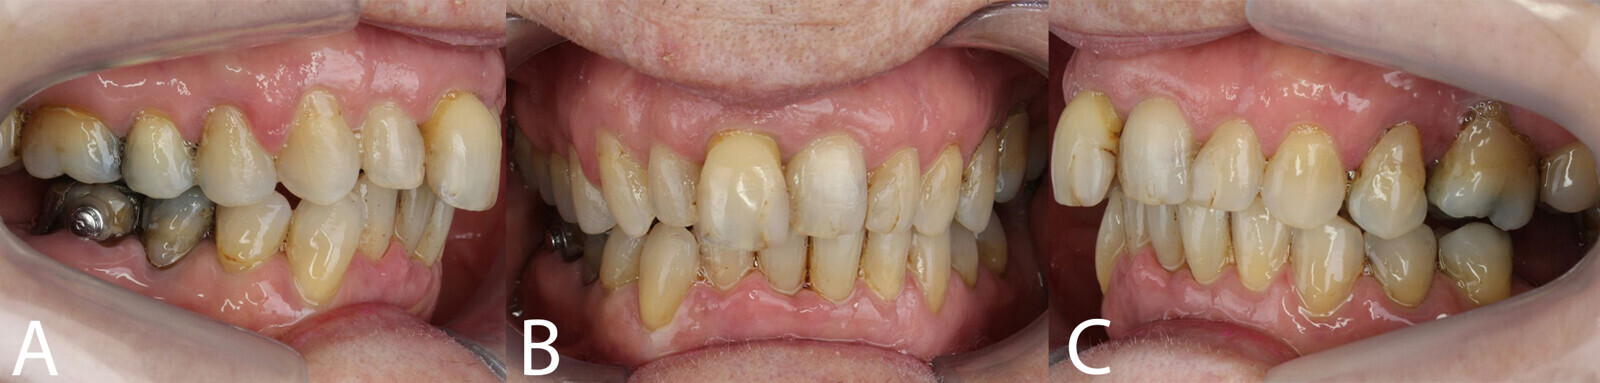

The periodontal treatment of an adult patient undergoing treatment with aligners is illustrated in demonstration of these points. Orthodontic planning considered the extra-oral photographs (Fig. 1) and intra-oral photographs (Figs. 2 & 3). Intra-oral scanning (Fig. 4) and radiographic documentation using panoramic radiographs and cephalometric radiographs (Figs. 5 & 6) were also carried out. From a periodontal perspective, periapical radiographs were recommended (Fig. 7), as this was an adult patient who smoked and showed clinical signs of advanced periodontal disease. Prior periodontal treatment was carried out (Fig. 8) to begin treatment with aligners (Fig. 9).